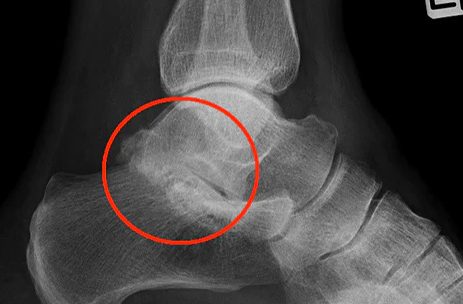

Subtalar Arthritis

Subtalar Arthritis is generally categorized as pain in the hindfoot. The subtalar joint is the joint that lets you rotate your foot back and forth and bend it back and forth. Patients who suffer from Subtalar Arthritis will feel pain when walking or moving the ankle. WHAT CAUSES SUBTALAR ARTHRITIS? Subtalar Arthritis is usually caused by a fracture in the foot, usually the heel bone. It can also be caused by excessive wear and tear on the joints resulting from too much activity. HOW DO I KNOW IF I HAVE SUBTALAR ARTHRITIS? WHAT ARE THE SYMPTOMS OF SUBTALAR ARTHRITIS? The most common symptom of Subtalar...